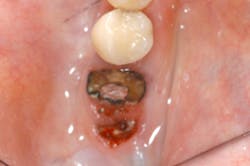

If one is taking certain osteoporosis medications and needs any kind of oral surgery, serious problems could occur. We were made aware of bisphosphonate-related osteonecrosis of the jaw (BRONJ), however, bisphosphonates are not the only culprits. An increasing number of osteonecrosis cases involving the maxilla and mandible have been associated with other antiresorptive (e.g., denosumab) and antiangiogenic therapies. (2) Therefore, the American Association of Oral and Maxillofacial Surgeons (AAOMS) feels it is more appropriate to label this condition medication-related osteonecrosis of the jaw (MRONJ). In 2013, a special committee met to evaluate the current literature and revise the 2009 guidelines to reflect current knowledge in this field. The update contains revisions to diagnosis, staging, and management strategies, and highlights current research status. (2)

MRONJ adversely affects the quality of life, causing significant morbidity. Protocols for management of patients with MRONJ, or those at risk for it, were presented in the AAOMS updated Position Paper on Bisphosphonate-Related Osteonecrosis of the Jaw in 2009. (3) The new Position Paper is extremely detailed, and includes background material, risk factors for MRONJ, management strategies for patients treated with antiresorptives or antiangiogenics, treatment goals, and much more. (2)